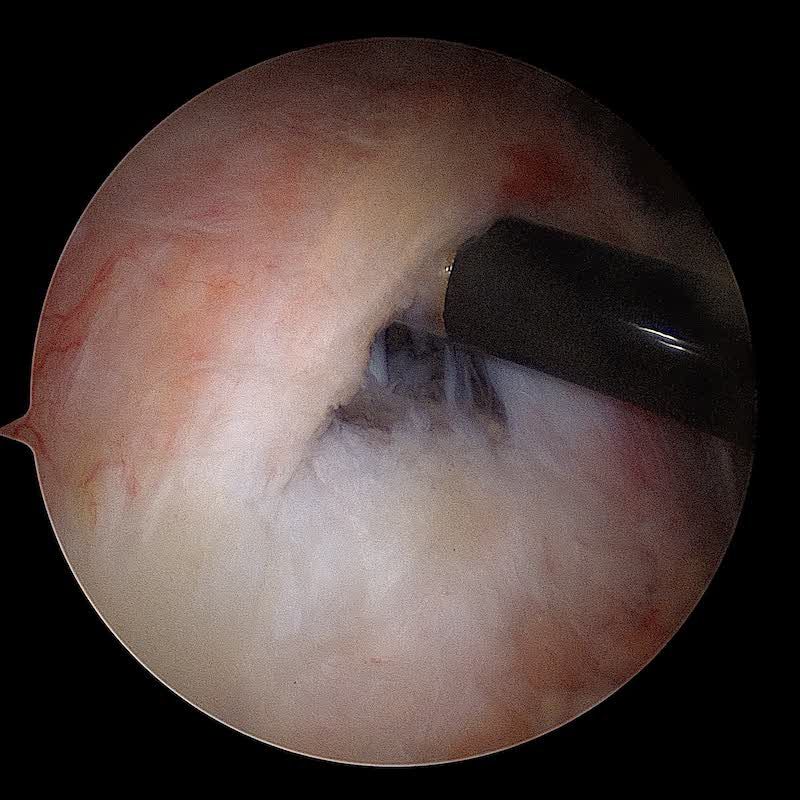

On utilise ensuite un pointeau qui permet de forer un orifice dans l'humérus . C'est dans cet orifice que va être placée l'ancre miniaturisée sur laquelle sont fixés les fils.

L'ancre sur laquelle sont fixées les sutures est vissée. Nous utilisons des ancres en PEEK et des ancres résorbables. Nous évitons dans la mesure du possible d'utiliser des ancres métalliques.